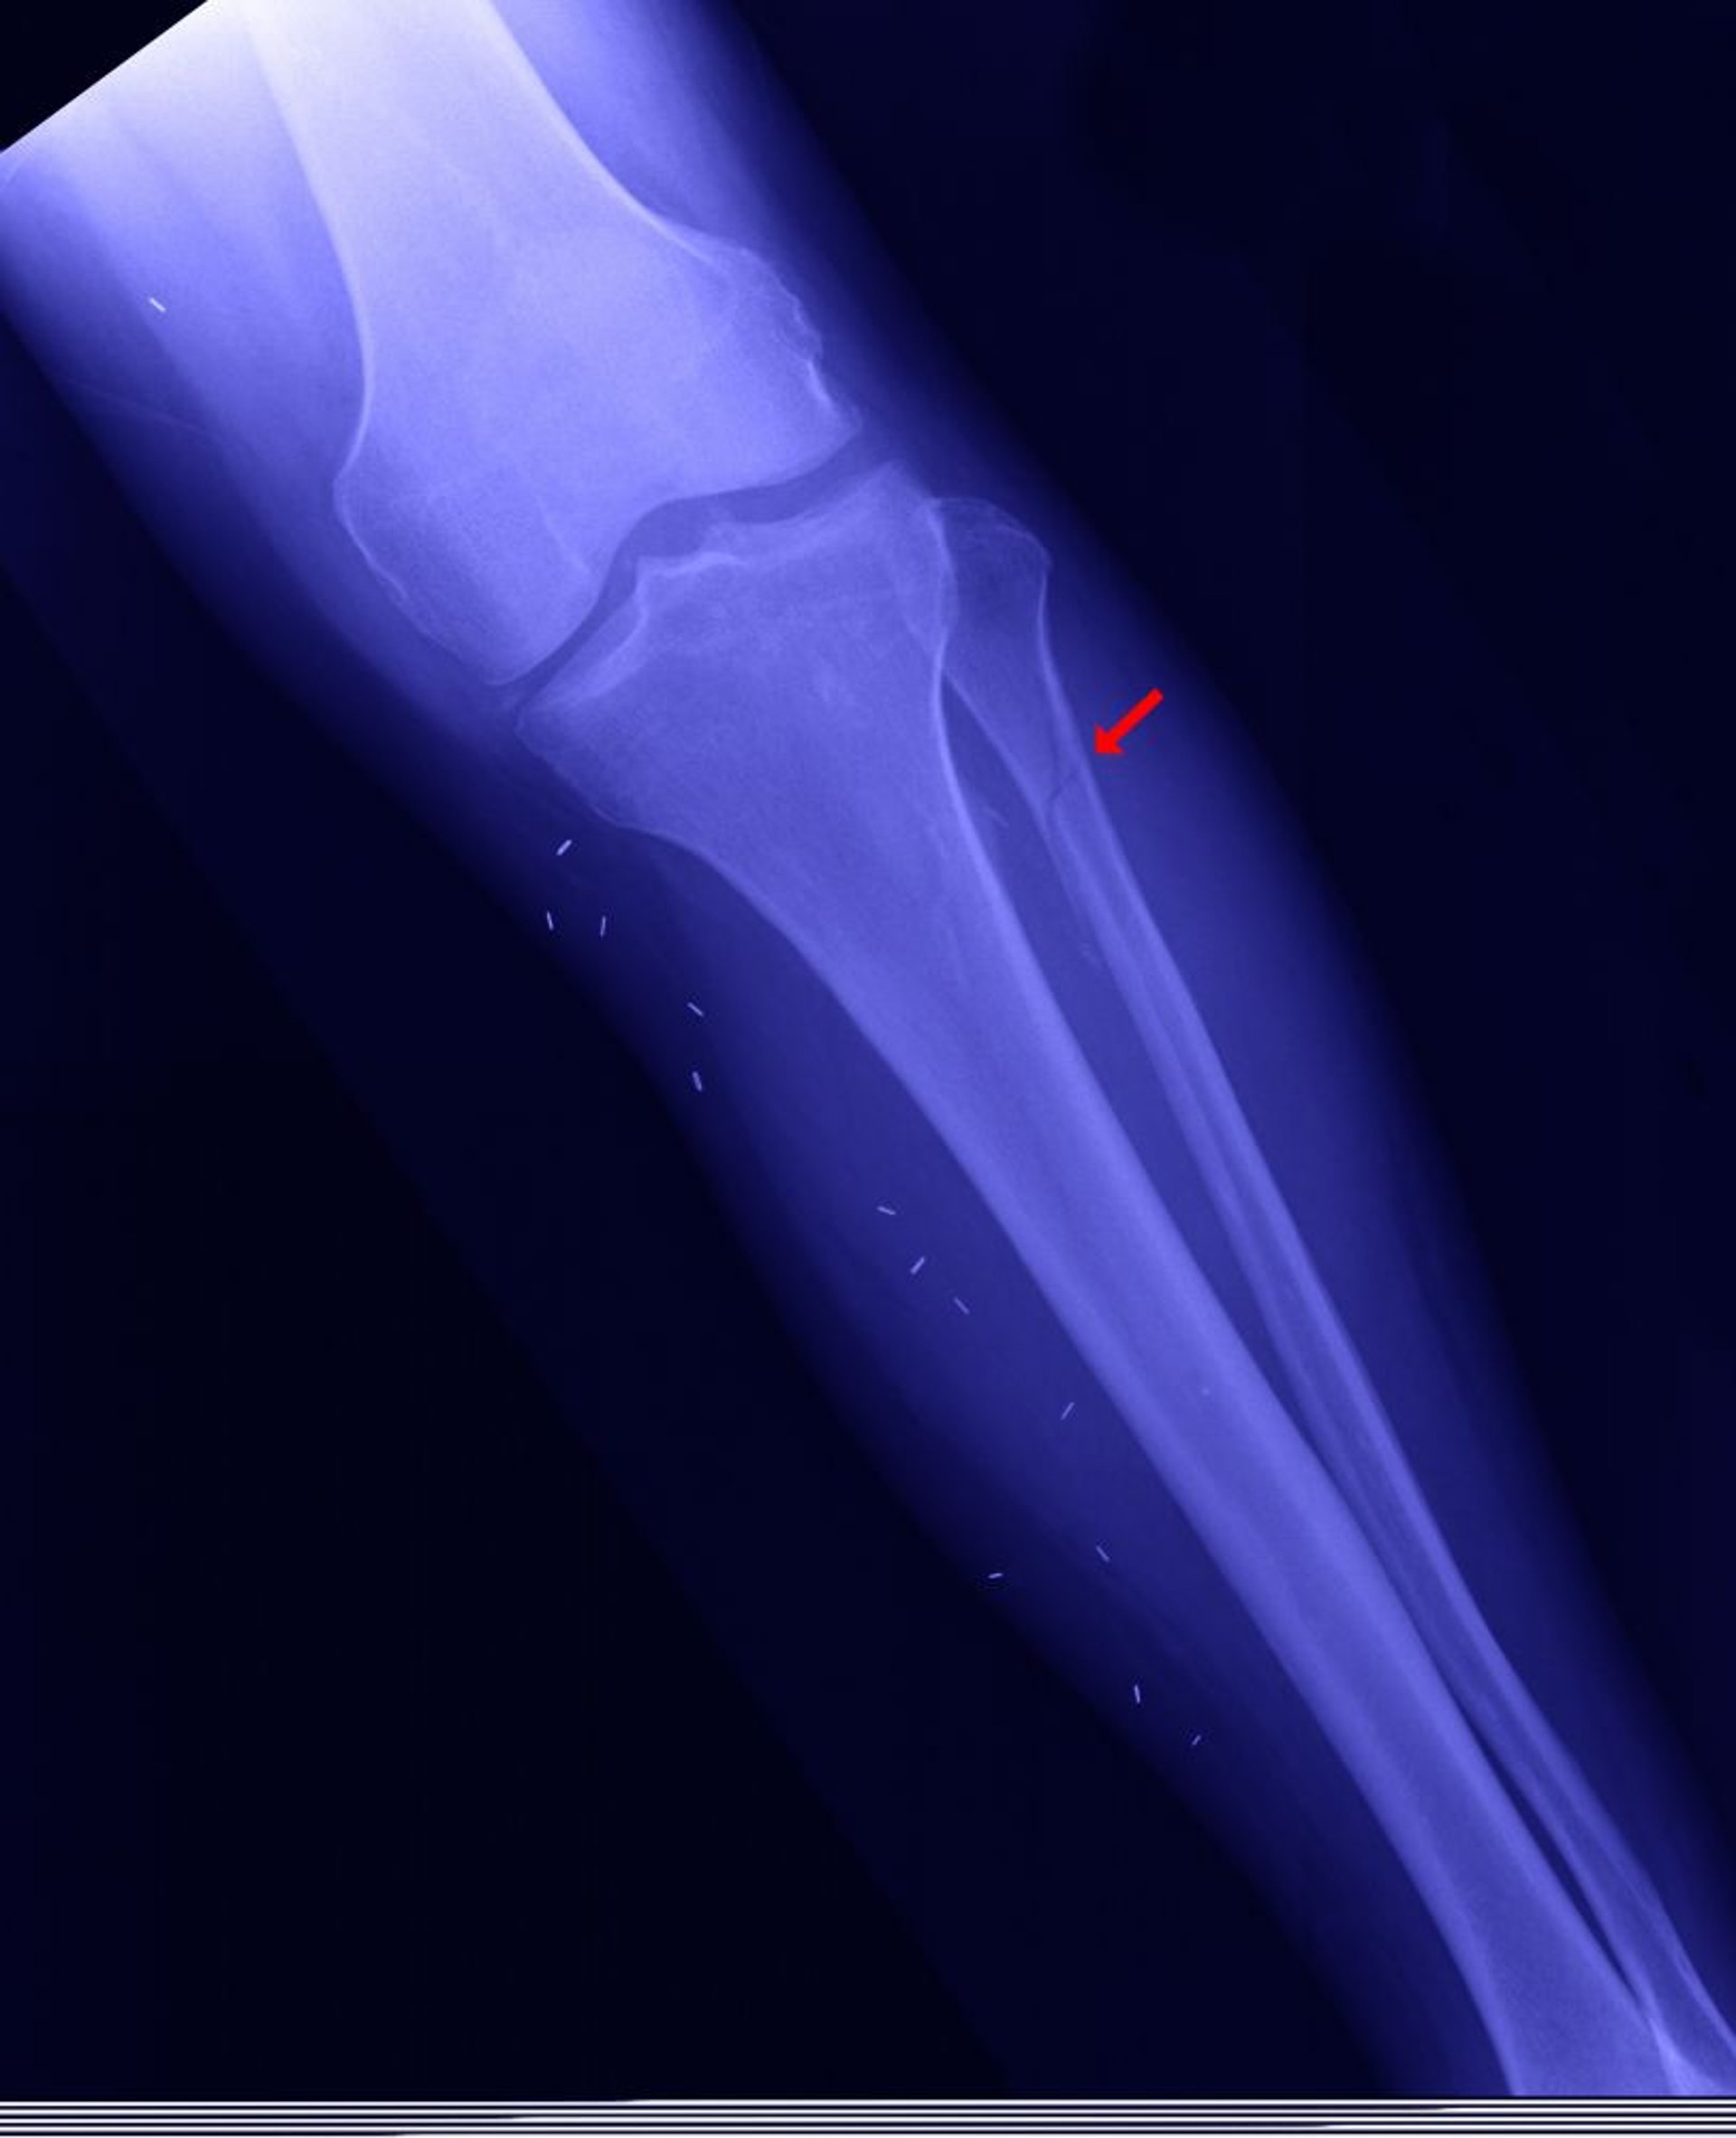

Fratura fibular proximal

A fíbula proximal pode ser fraturada (chamada fratura de Maisonneuve — mostrada aqui), quando o maléolo medial é fraturado, o encaixe do tornozelo (articulação entre a tíbia e o tálus) está aberto, e a fíbula distal não está fraturada.

EDWARD KINSMAN/SCIENCE PHOTO LIBRARY